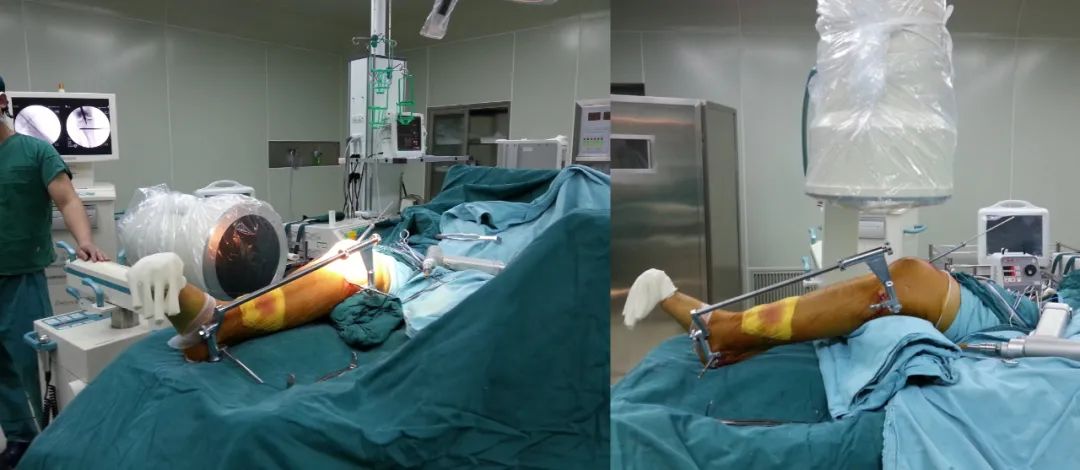

最终选择髌骨上入路髓内钉固定。

技术要点

1、使用牵开器维持骨折端基本的对位,对线。省时,省力不吃射线。

2、近端通过阻挡钉技术辅助骨折断端复位。

3、使用特殊的「 锁定型髓内钉 」远端即便只锁 2 枚锁钉依然稳定。